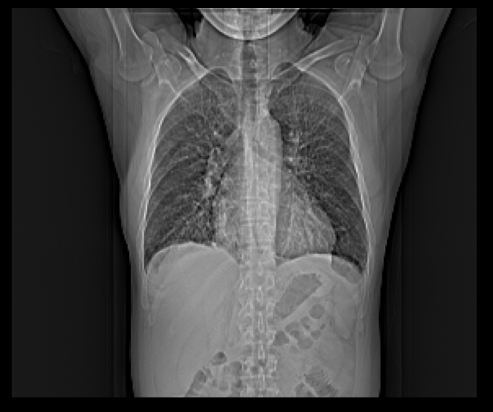

Das is natürlich auch möglich!ist ein Sportlerherz